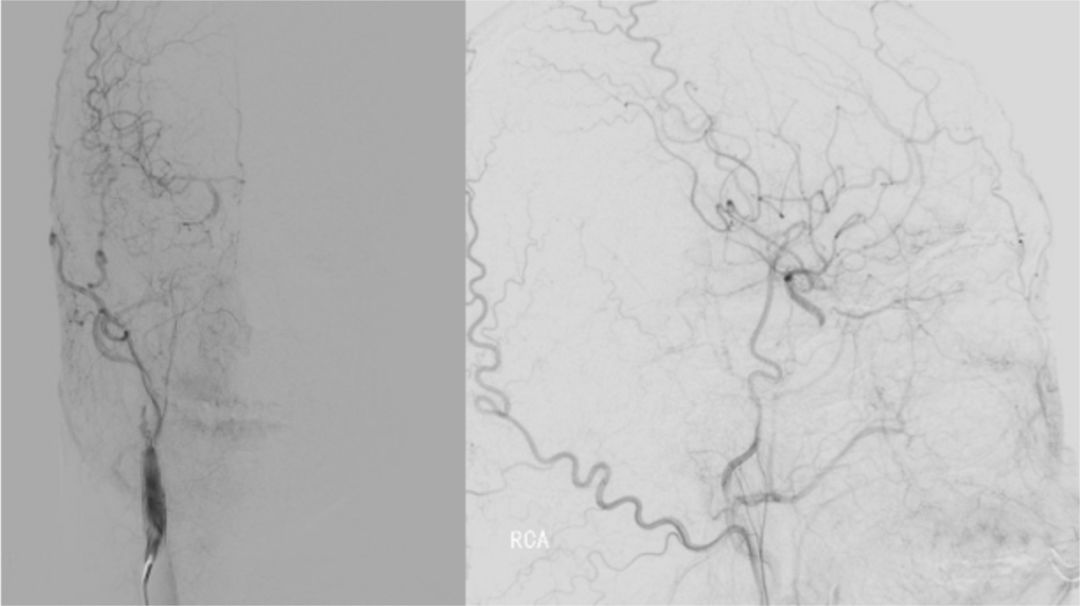

2019-06-07外院DSA:右侧颈内动脉闭塞(图2)。

图2

常规消毒铺巾,右侧股动脉穿刺成功,置入9F动脉鞘。150 cm超滑泥鳅导丝携5F单弯造影管分别行双侧颈总、左侧椎动脉正侧位造影,结果显示右侧颈内动脉C1-C4段闭塞,右侧颈外动脉侧枝向右侧眼动脉代偿供血,并反流至右侧颈内动脉颅内段,右侧大脑中、前动脉显影变淡(图5)。14∶50肝素4 000单位入壶,在长交换260 cm泥鳅导丝导引下将MOMA先端置于右侧颈外动脉,撤出泥鳅导丝。路径图下,PILOT50微导丝(0.014"x190 cm)携带Headway 21微导管沿MOMA送入右侧颈内动脉,微导丝通过闭塞段,微导管通过困难(图6)。

图5